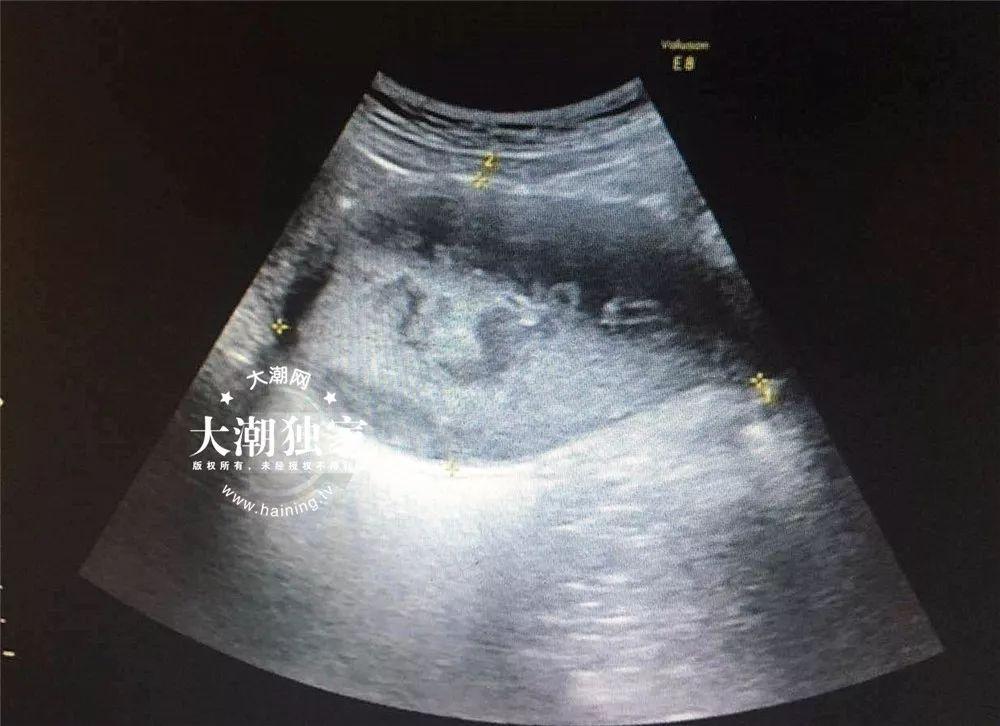

小燕到底怎么了?接诊的医生询问了小燕的病情后,当场就觉得小燕的情况有些特别,于是马上给小燕安排了B超和妇科检查。

△小燕的B超报告

根据检查,医院妇科主任俞丽娟判断,小燕得了处女膜闭锁伴盆腔感染!需要马上住院进行手术治疗。